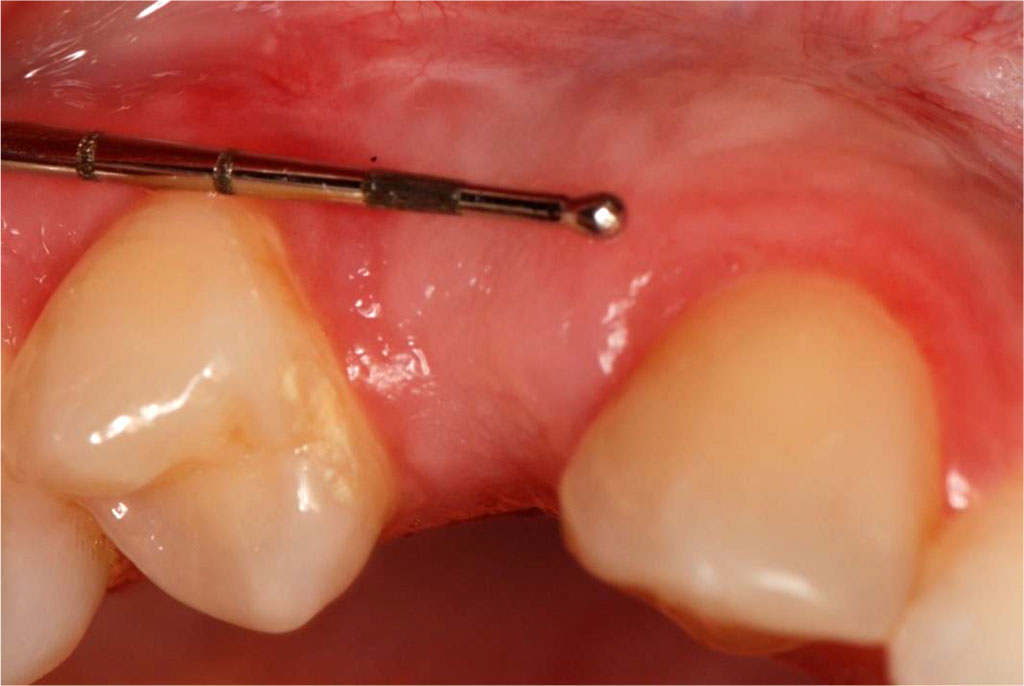

The patient, aged 42 was reffered from another dental office for peri-implant soft tissue augmentation in the aesthetic zone of the maxilla in the area of the implant located in position 13. Her history included type 2 diabetes, pharmacologically stabilised (she was taking Metformin 750mg twice a day), and no known allergies. Family history, no genetic burden. On extraoral clinical examination, no apparent facial asymmetry, chin and submandibular group A lymph nodes not palpable, not painful. Trigeminal nerve outlets not painful. No pathology in the temporomandibular joint. Intraoral clinical examination revealed a thin gingival biotype and a insufficient transverse gingival dimension in the vicinity of the implant at the crown neck of tooth 13, with no signs of inflammation, bleeding, bacterial plaque or pathological depths at the 6 points examined around the implant (Fig.1). The thickness of the keratinised gingiva at the implant at position 13 was measured by ultrasonography. The thickness of the keratinised gingiva was 0.75 mm (Tab.1). The width of the keratinized gingiva in the specified area was 1 mm (Tab.1).

Fig.1 The condition of the peri-implant soft tissues before sCTG augmentation.